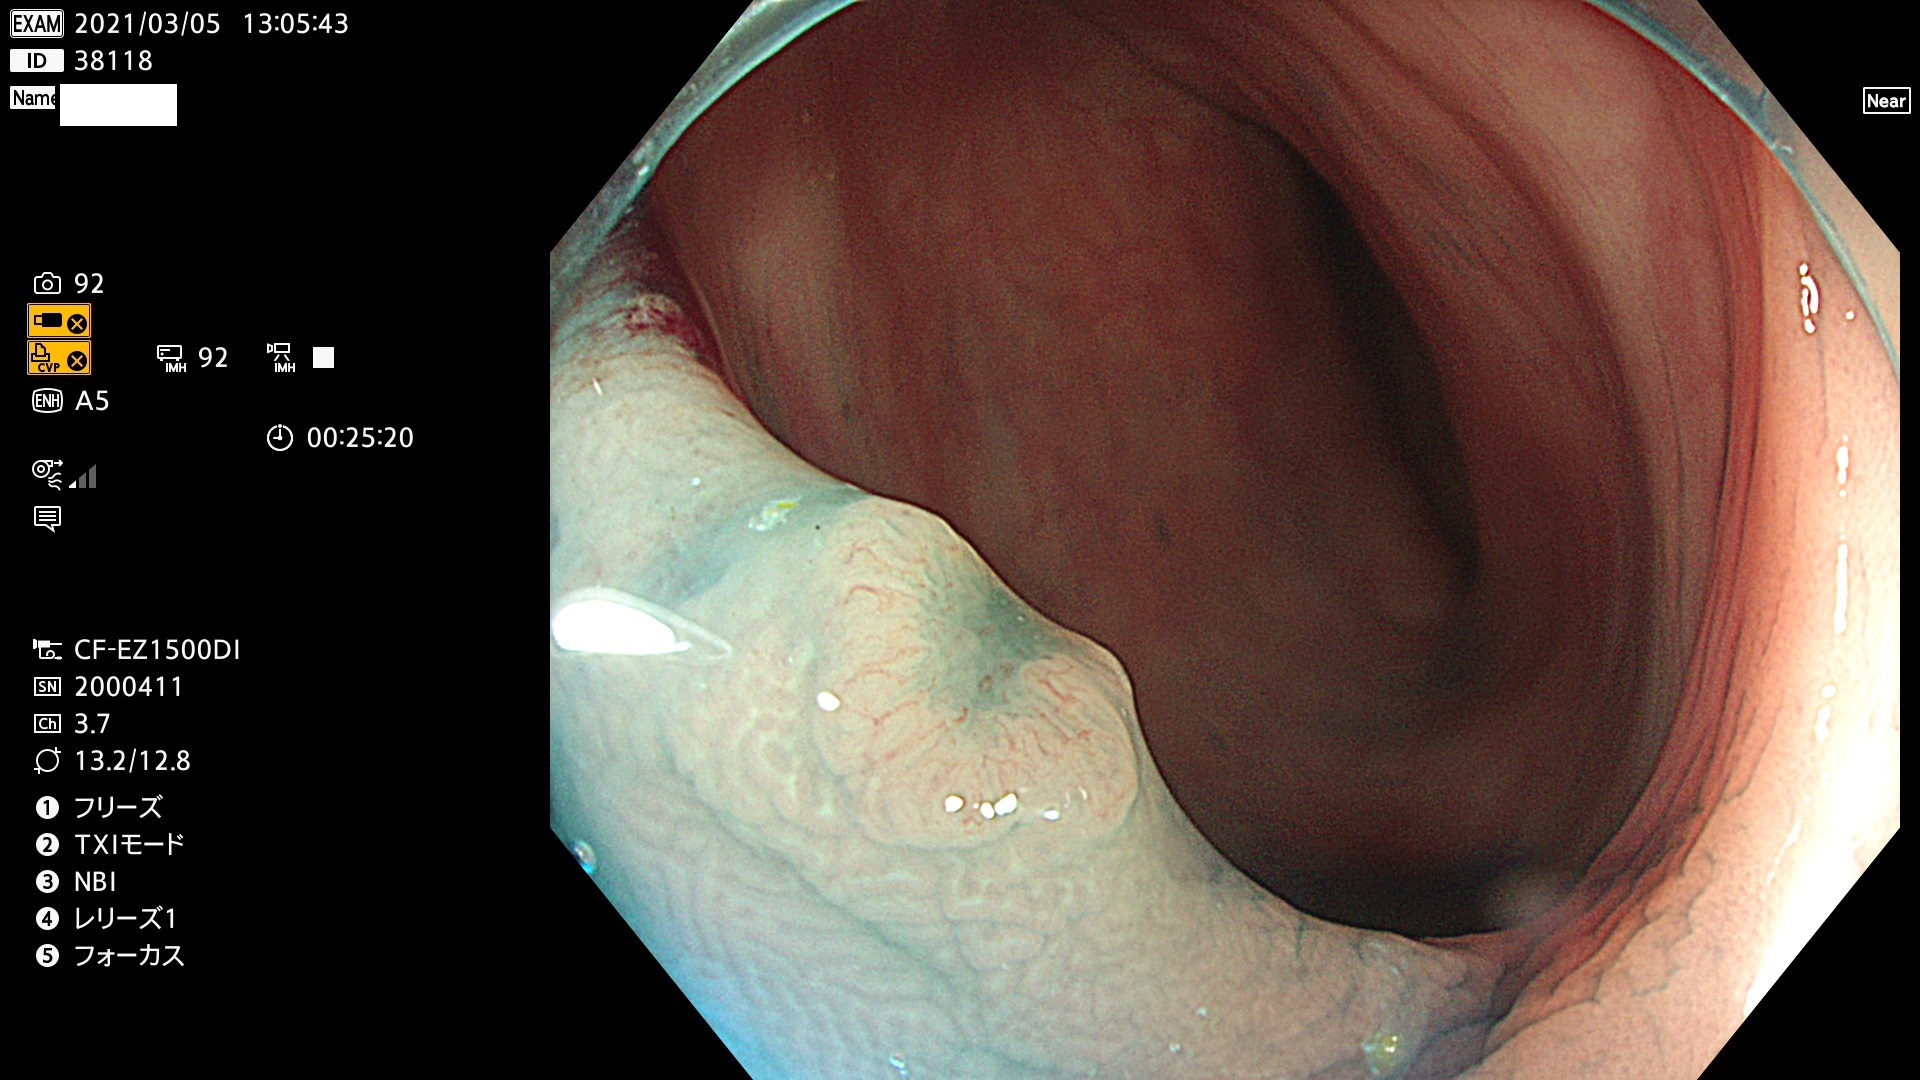

腺腫発見率 72 % (カルテ番号 38100〜38199の100名の方の検査結果で集計)大腸癌検診最新情報

以下のカルテ番号の方に腺腫(Adenoma,Group3〜5)が見つかりました(集計法)

38101 38103 38104 38106 38107 38108 38109 38110 38111 38112 38113 38114 38115 38117 38118 38122 38123 38124 38125 38126 38127 38128 38130 38131 38132 38135 38137 38138 38140 38141 38142(SSAPのみ) 38143 38144 38145 38146 38147 38148 38149 38150 38151 38152 38153 38154 38157 38158 38160 38161 38162 38164 38165 38166 38167 38168 38169 38172 38176 38177 38178 38181 38182 38183 38184 38187 38189 38190 38191 38192 38193 38194 38195 38196(SSAPのみ) 38198

発見困難で危険性の高い平坦型病変(上記100名より抽出) ![]()